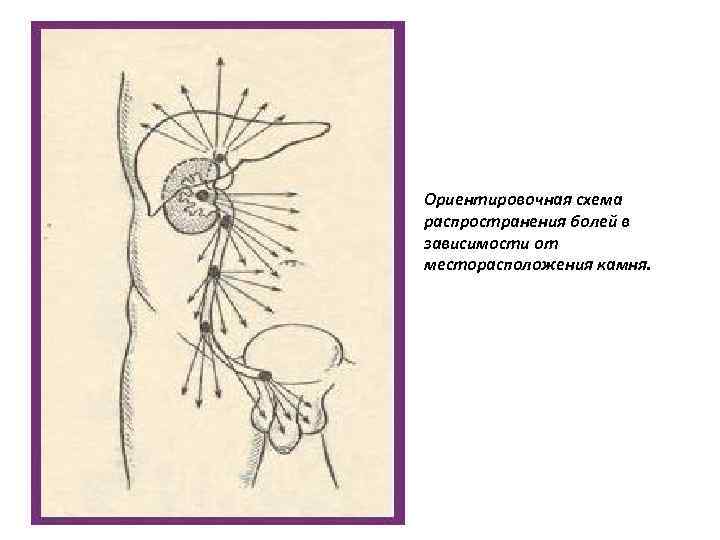

Ориентировочная схема распространения болей в зависимости от месторасположения камня.